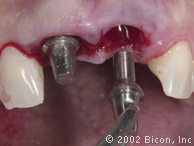

Установка двух 5.0mm x 8.0mm HA имплантантов Bicon

Определение направления оси и глубины шахты имплантантов

Abutment Shoulder Gauge

Вид после установки